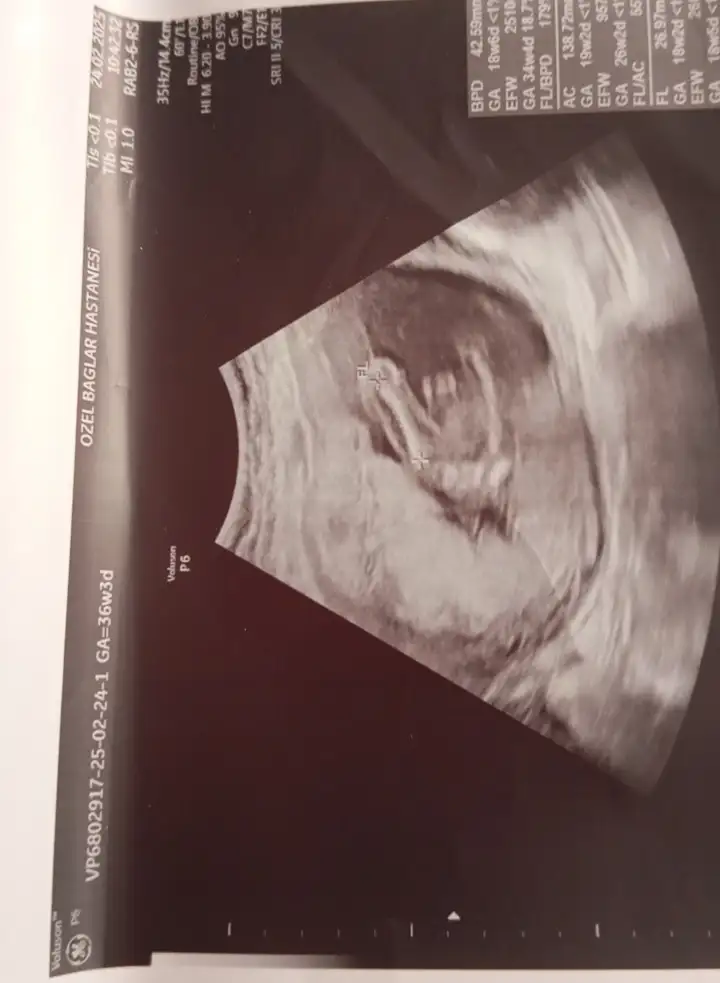

Bunlarada bakar mısınız lütfenErkek canım

Bunlarada bakar mısınız lütfenEvet erkek bu bebiş